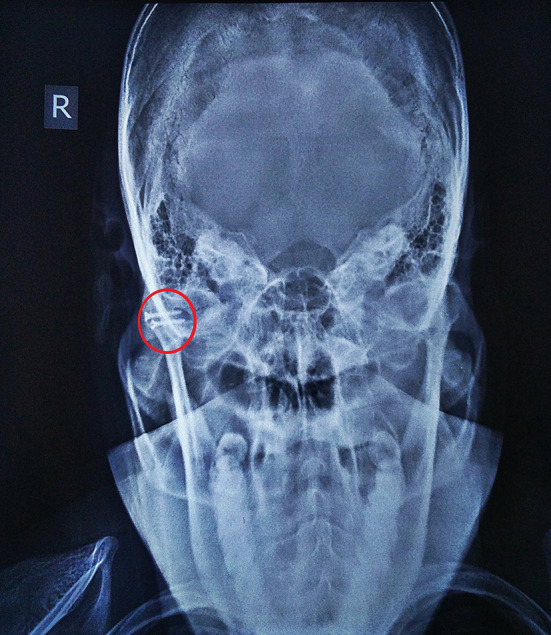

Fig. 1.

Arrow showing the bilateral head of the condyle fracture in coronal view of computed tomography. Measurements were made to determine the length of the lag screw for open reduction internal fixation